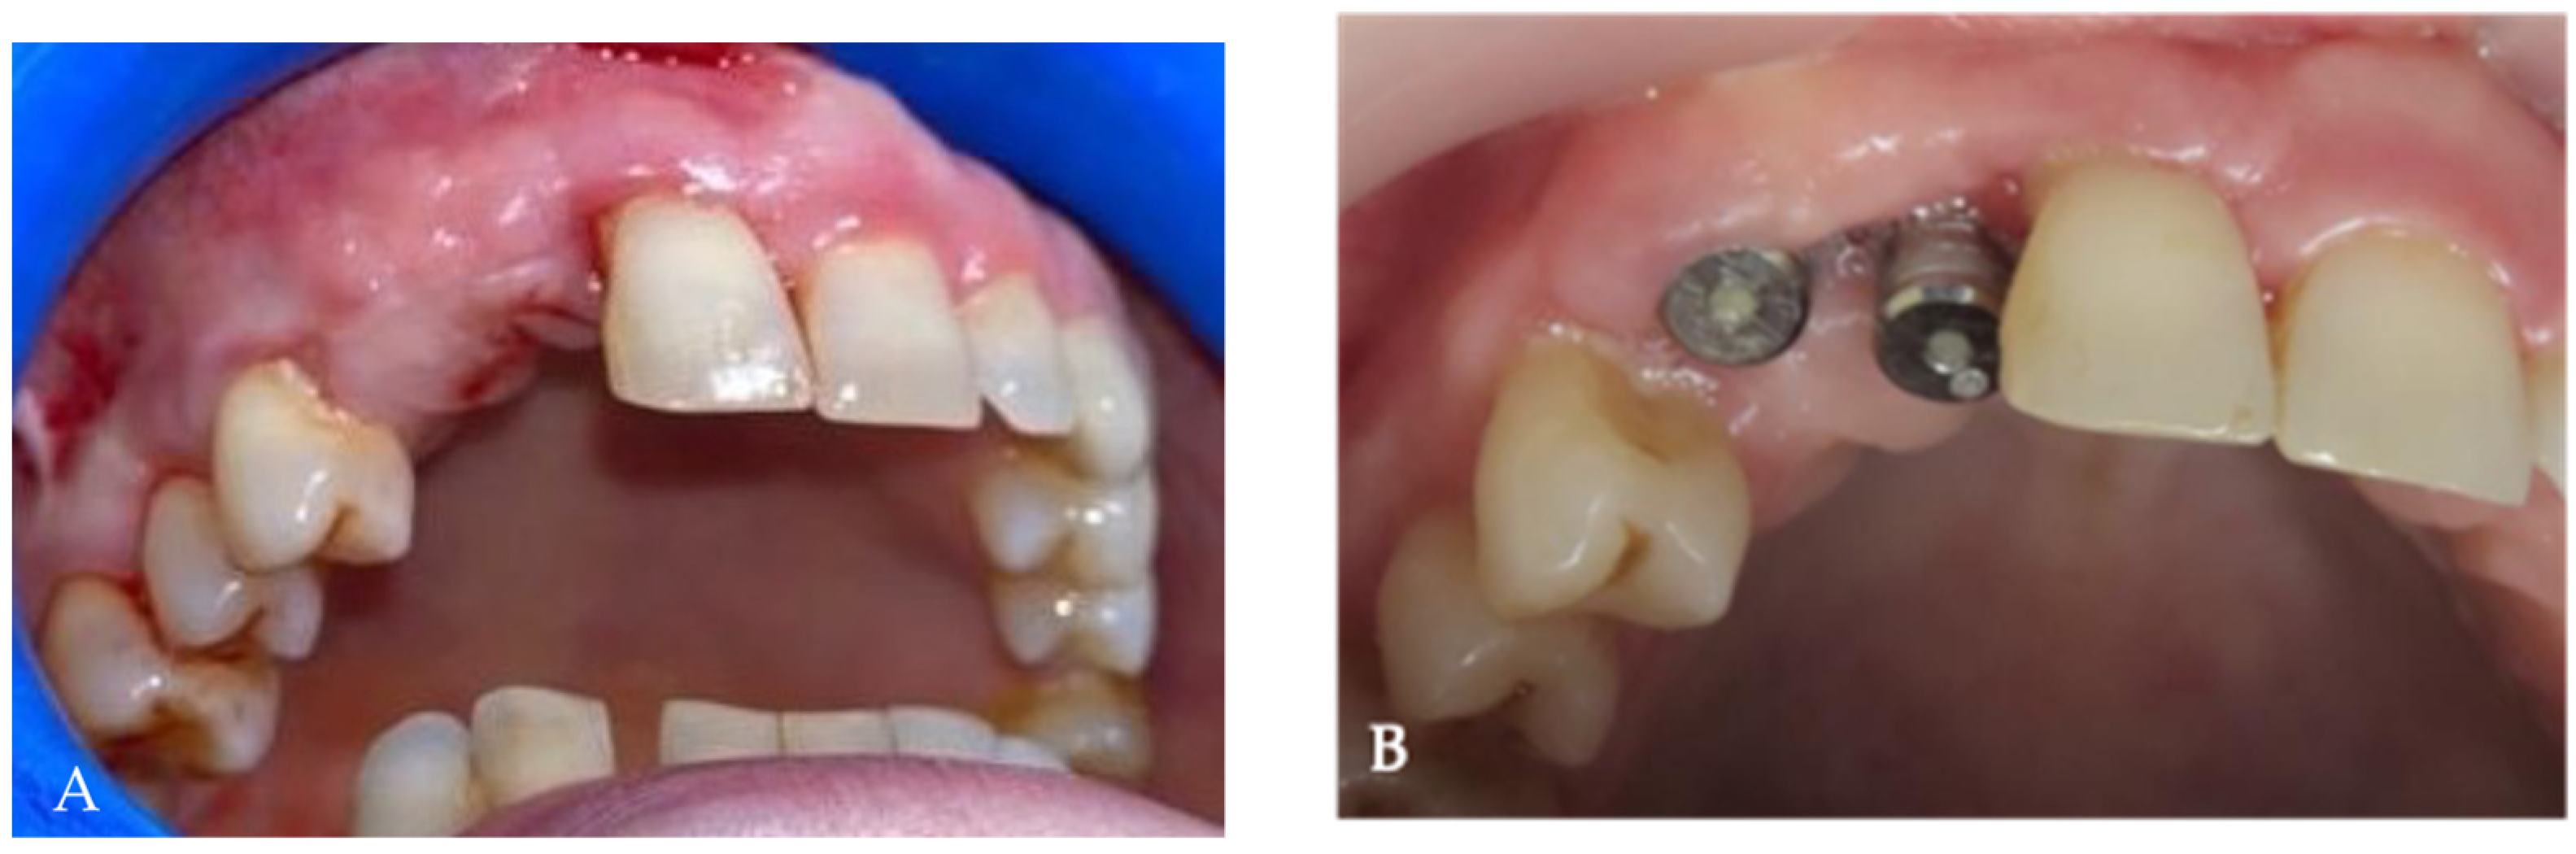

2. Case Presentation